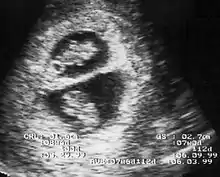

En France, selon les recommandations de la HAS de 2009, révisées en 2016[8], le diagnostic de grossesse gémellaire est effectuée lors de l'échographie du premier trimestre. Cet examen doit déterminer aussi la chorionicité, car elle devient de plus en plus difficile à préciser avec l'évolution de la grossesse. Ce premier examen permet de distinguer les grossesses bichoriales de bon pronostic, et les grossesses monochoriales, plus à risques de complications. Chacun des jumeaux doit être suivi selon les examens réalisés habituellement lors d'une grossesse unique (par exemple : dépistages d'un retard de croissance intra-utérin, d'une trisomie 21, de malformations...)[6].